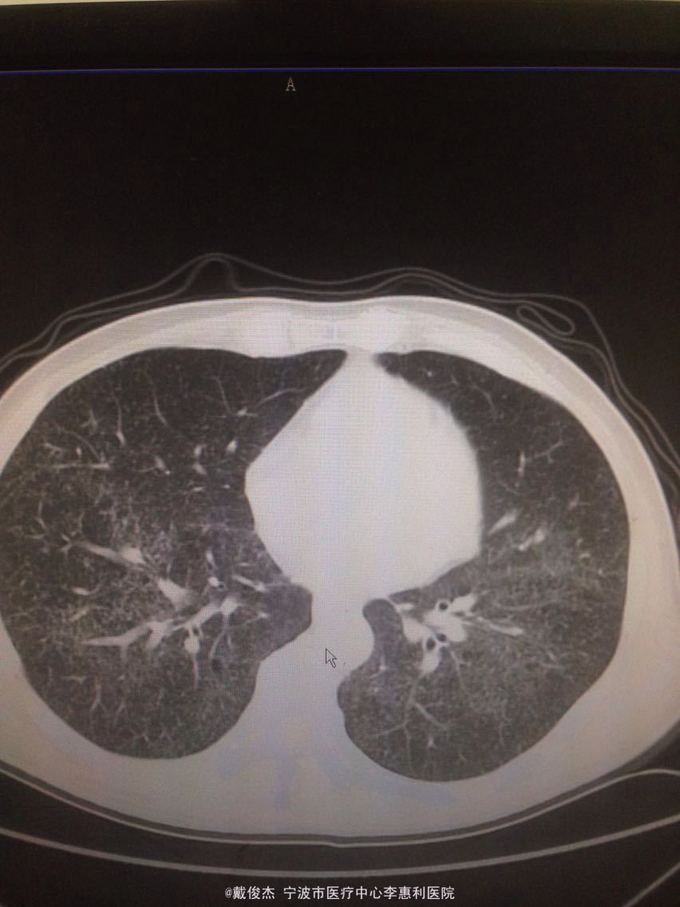

患者,男,主诉:反复发热2月,再发伴头痛12天 病史:2月前出现发热,伴咳嗽、咳痰,12天前出现头痛

查体:神志清,双肺啰音,颅神经阴性,颈抵抗,四肢肌力正常,双巴氏征阴性 辅查:脑脊液压力380mmH2O,细胞4100/ul,多核90%,单核10%,蛋白223mg/ml。胸部CT示:两肺多发粟粒小结节。头颅MRI示:双侧大脑半球、脑干、小脑多发病灶。

诊断:结核性脑炎,肺结核 处理:抗痨治疗,激素,降颅压,保护神经和对症支持治疗

该患者考虑肺结核致结核性脑炎